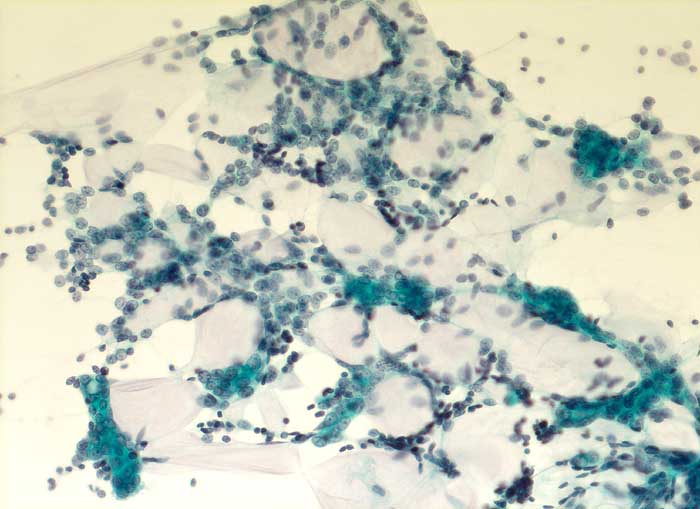

Einleitung

Adenoidzystische Karzinome machen lediglich 1% aller Mammakarzinome aus. Die Morphologie ist identisch mit dem gleichnamigen Tumor der Speicheldrüsen. Die Zellen des adenoidzystischen Karzinoms bilden kohäsive Verbände und Drüsen oder mikrozystische Strukturen. Die Tumorzellen sind klein und monomorph, die Kern-Zytoplasmarelation ist hoch. Die Kerne sind dunkel, rund bis oval oder angulär und enthalten bisweilen einen kleinen Nukleolus. Azelluläre hyaline Körperchen aus mucoidem Material, welche die Hohlräume der intakt aspirierten kribriformen Strukturen ausfüllen, sind besonders typisch. Das mucoide Material kann auch verzweigte oder fingerartige abgerundete Strukturen ausbilden.